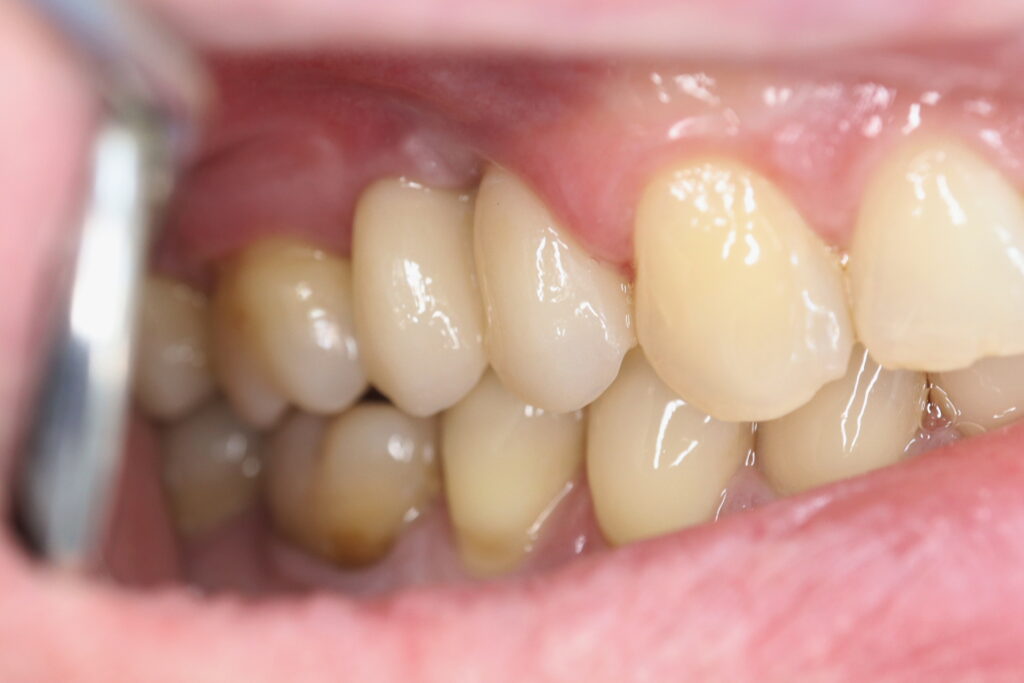

Также на нижнюю челюсть был изготовлен мостовидный протез из 4х коронок (цирконий) с опорой на 3 индивидуальных абатмента с одной стороны и 1 коронка на иплантат с другой.

Пациенту были установлены 6 имплантатов Megagen AnyOne по системе All-on-6 на верхней челюсти и 4 имплантата на нижней по классической двухэтапной методике.